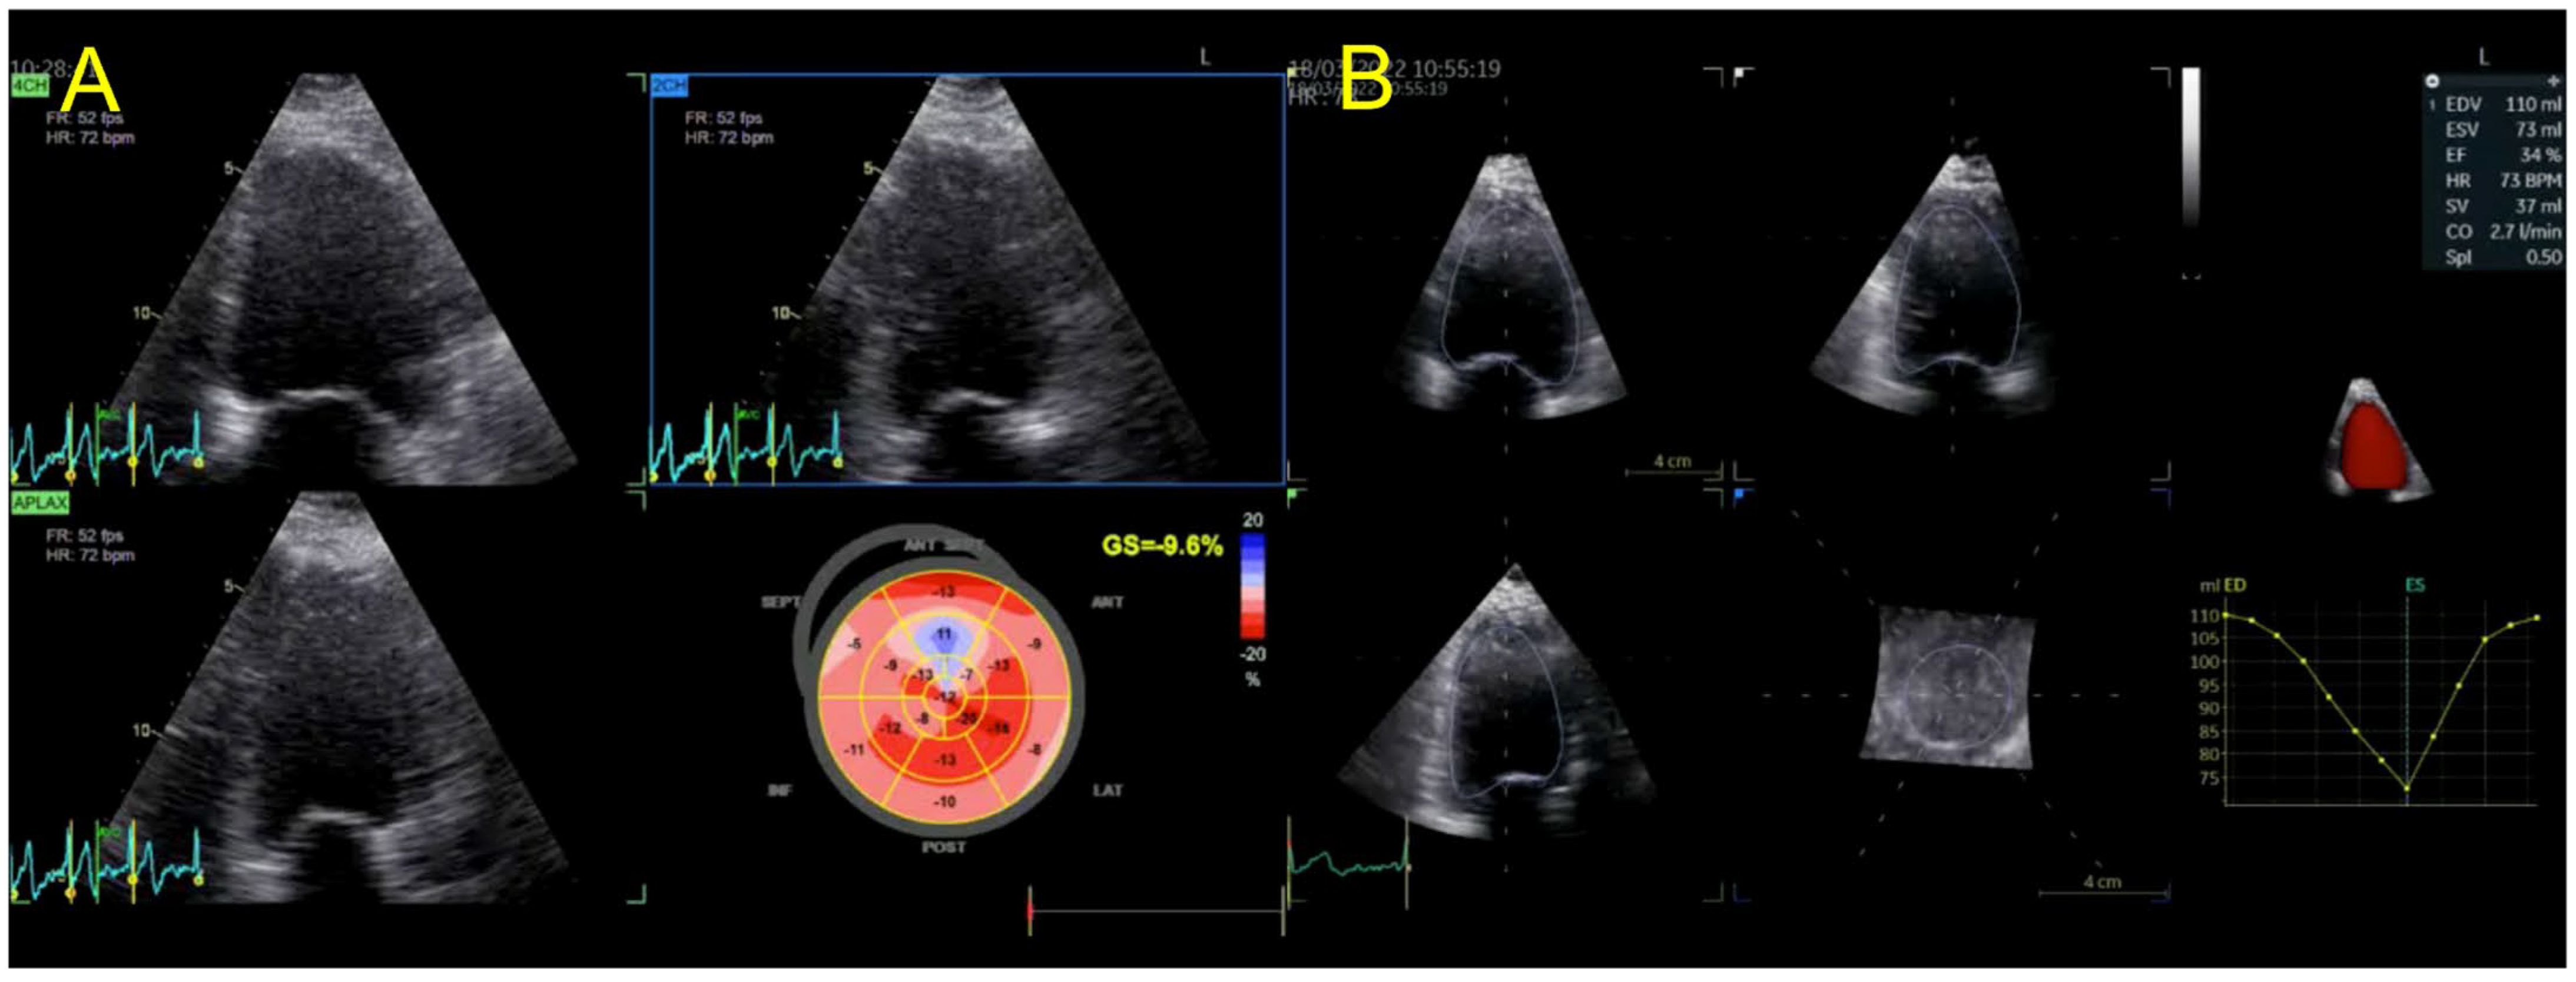

| Echocardiography | Hypokinetic non-dilated cardiomyopathy LVEF = 42% Mild mitral regurgitation IAS aneurysm | Hypokinetic non-dilated cardiomyopathy LVEF = 34% Mild mitral regurgitation IAS aneurysm | Left ventricular concentric hypertrophy LVEF = 54% |

| Cardiac magnetic resonance imaging | Hypokinetic non-dilated cardiomyopathy Left ventricular non-compaction LVEF = 50% | Hypokinetic non-dilated cardiomyopathy Regional sub-epicardial fibrosis LVEF = 41% | Not carried out |